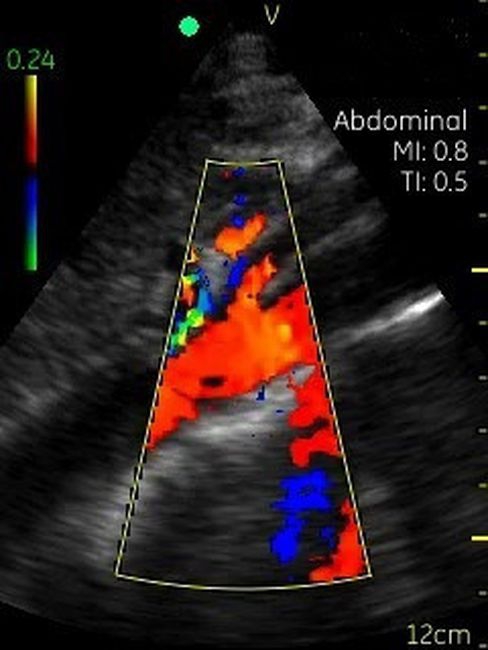

Невозможно было представить раньше, что УЗИ аппарат может помещаться на ладони руки человека. Теперь это реальность, воплощенная в корпусе и технологической начинке GE VSCAN. Инженеры заложили возможность получения дополнительной визуализации кровотока с цветной кодировкой в режиме реального времени для полноценной постановки диагноза на месте.

Визуализация Vscan:

· Наложение кровотока с цветовой кодировкой в реальном времени.

· Сектор цветного режима показывает кровоток с углом обзора 30 градусов